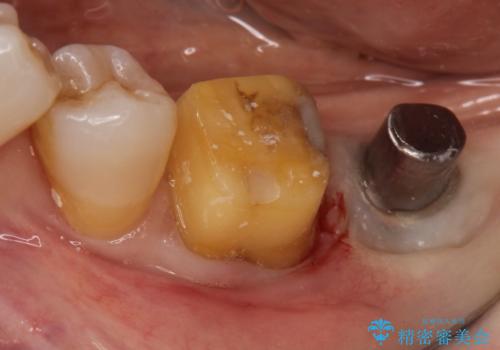

- 左下の1番後方の歯が欠損しており、インプラントにて咬合回復する計画としました。

レントゲン・CT撮影により骨の高さがあまりないことがわかり、ショートインプラントを選択しました。

また、清掃性を確保するために歯肉の移植も行うこととしました。